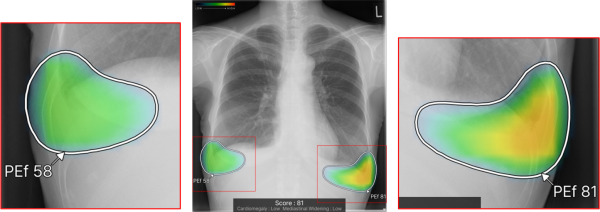

ヒートマップ/輪郭表示機能

異常所見の存在可能性(確信度)を、青から赤へのグラデーションで示すヒートマップ表示について、多くの利用者からご好評いただいている。一方、モノクロモニタを利用する一部の読影環境では、淡いヒートマップが確認しにくいという課題があった。新バージョンでは、異常所見の疑われる領域の表示方法として、「ヒートマップ表示」「輪郭表示」「ヒートマップと輪郭の併用表示」の3つの表示パターンが選択可能になった。これにより、各施設の運用環境に応じた最適な表示方法を利用できる。

従来のバージョンでは、複数の異常所見を検出した場合、検出された異常所見のうち最も確信度が高い所見のスコアのみを表示しており、各所見のスコアを確認したいという要望があった。新バージョンでは、各検出領域に対応する所見名と確信度を示すスコアを個別に表示できるようになった。これにより、医師は複数の異常所見について詳しい情報をひと目で把握でき、正確な診断を行うことが期待できる。

また、従来のバージョンでは、対象所見が重なった領域においてヒートマップが重なって表示されていまた。そのため、異なる所見が混在している部分の識別が難しく、細かな判別や詳細な確認には限界があった。これに対し、新バージョンでは、対象所見が重なった領域についても、各所見ごとに独立した輪郭線を表示できるようになった。複数の異常所見が存在する箇所でも、それぞれの所見の範囲を明確に区別できるようになり、より詳細かつ正確な画像診断支援が期待される。